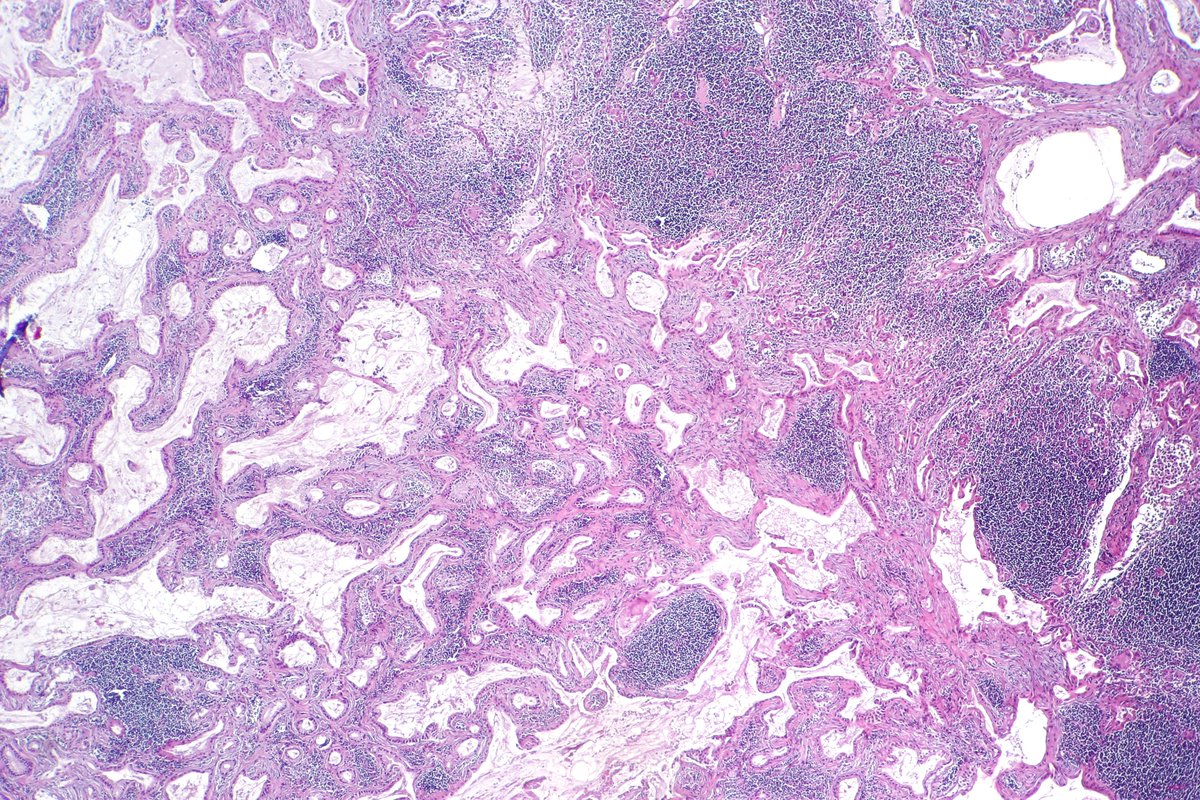

Pancreatobiliary-type adenocarcinoma lymph node metastasis showing well-formed, irregular glands associated with desmoplastic stroma. #pathology #GIPath